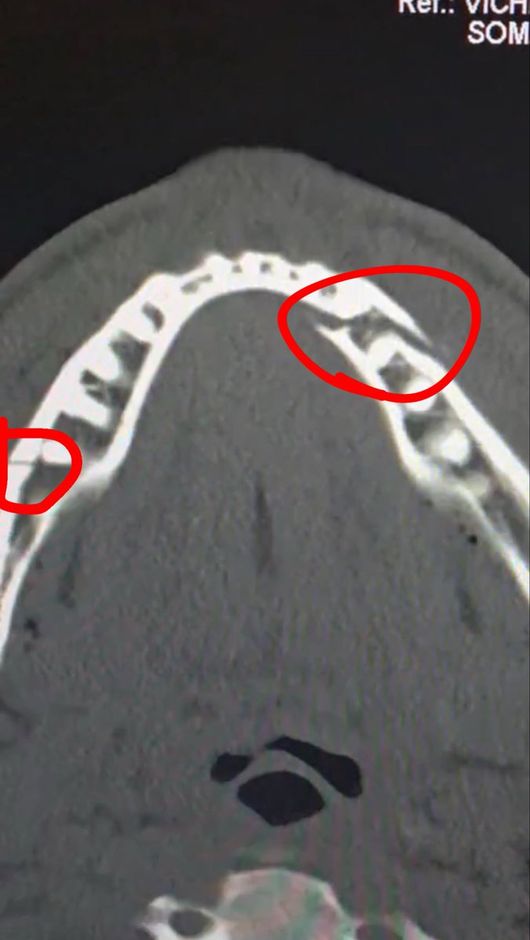

조슈아 측도 같은 입장이다. 조슈아의 프로모터인 에디 헌도 조작설을 정면 반박했다. 그는 "우리는 배우가 아니다. 이 싸움은 100% 진짜였다"라며 "폴의 턱이 두 군데 부러지고 치아가 여러 개 빠졌다는 사실을 알고 있는 건가? 그는 다시는 싸울 수 없을지도 모른다"라고 꼬집었다.

실제로 폴의 부상은 결코 가볍지 않았다. 진단 결과 그의 턱뼈는 두 곳이나 골절돼 세 동강이 난 모습이었다. 그는 곧바로 수술대에 올랐고, 티타늄 플레이트 두 개를 삽입했다. 치아도 일부 제거해 한동안 정상적인 식사도 불가능한 것으로 알려졌다.

폴은 소셜 미디어를 통해 자신의 수술 후 상태를 공개하면서 "통증이 심하지만 난 괜찮다. 턱뼈가 두 군데나 으스러졌다. 7일 동안 유동식을 먹어야 한다"라고 밝혔다. 경기를 앞두고 조슈아에게 "널 죽여버리겠다"라고 도발했던 폴이지만, 조슈아의 벽은 너무나 높았다.